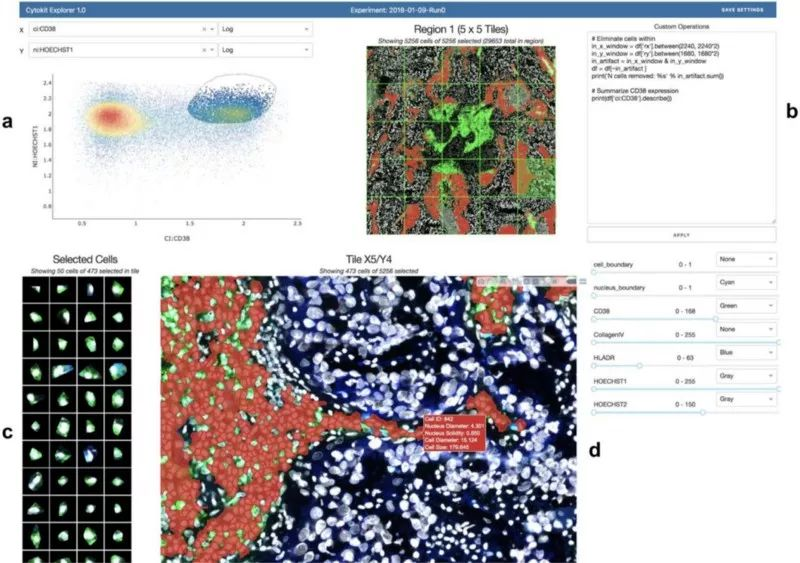

同样,南卡罗来纳医科大学的 Hammer 实验室正在开发一种带有 Dash 的开源细胞显微镜工具,并在 bioRxiv 上发表了他们的方法 (https://www.biorxiv.org/content/10.1101/746164v1.full):